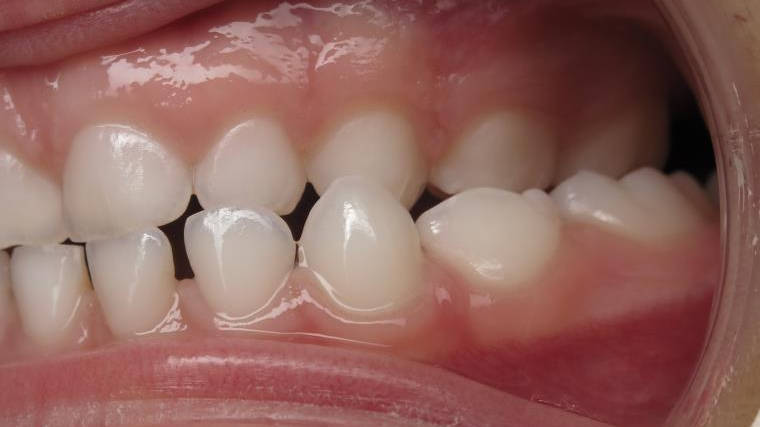

surveillance évolution de la dentition en cours

bilan début et en cours de traitement